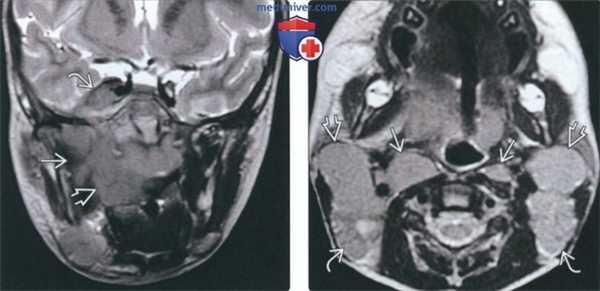

(Слева) На корональной МРТ (Т2 ВИ) определяется лимфома Беркитта, занимающая несколько смежных областей: пространство слизистой оболочки глотки, жевательное пространство задние отделы верхней челюсти справа.. Определяется также поражение Меккелевой полости.

(Справа) На аксиальной МРТ (Т2 ВИ) определяется нодальная лимфома Беркитта с поражением заглоточных ВЗ глубоких шейных э, добавочных спинальных лимфоузлов^. Лимфоузлы увеличены, признаки некроза отсутствуют.

4. МРТ при лимфоме Беркитта челюсти:

• Т1 ВИ

о Диффузная инфильтрация с гиподенсным сигналом

• Т2 ВИ:

о Сигнал неоднородной интенсивности: гипер-, изо-, гипоинтенсивный

о Участки фиброза гипоинтенсивны

• Т1 ВИ С+:

о Контрастирование позволяет оценить мягкотканный компонент и увеличенные лимфоузлы